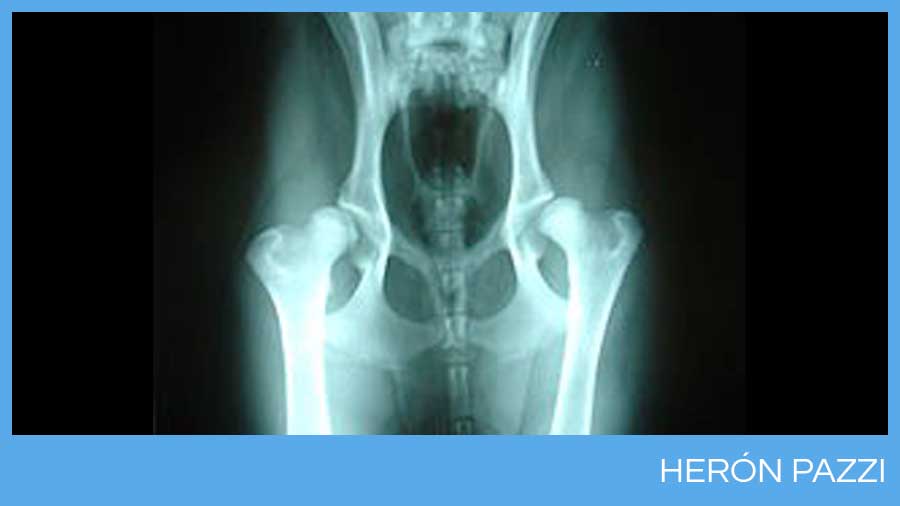

Cadera normal.

Displasia de cadera en un Labrador Retriver.